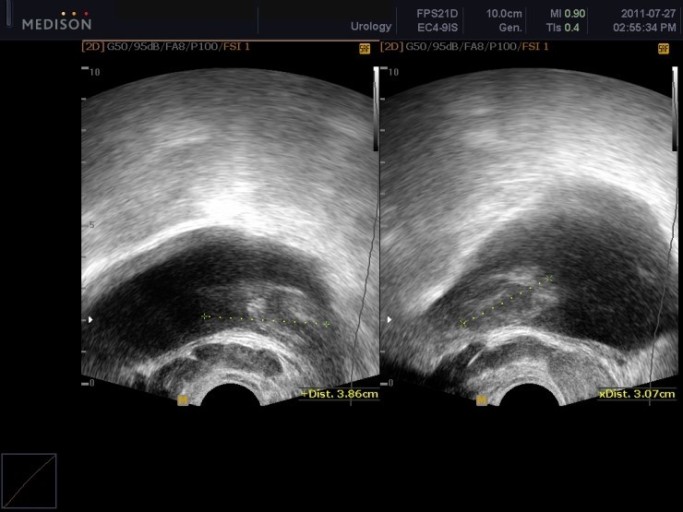

남자의 건강을 위협하는 대표 질병 중 한 가지는 전립선 질병이다. 전립선염은 남자의 50%가 일생에 한 번은 겪어볼 정도로 흔한 질병이 됐으며, 전립선암은 최근 20년간 20배 넘게 증가할 정도로 대중적인 질환이 되었는데요.